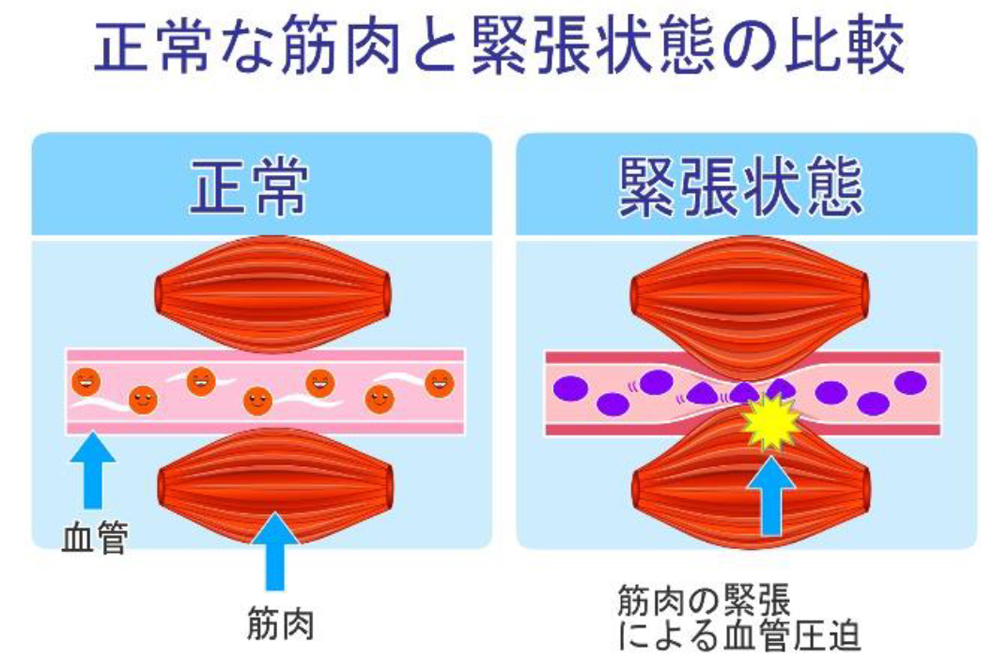

■原因① 筋肉の緊張と血行不良

首の痛みの大部分は、姿勢の悪さからくる筋肉の緊張や血行不良が関係しています。首や背中が緊張するような無理な姿勢や、猫背での作業や長時間のデスクワークでの姿勢が影響して、脊椎のS字カーブが崩れます。そして、頭をきちんと支えられずに首と肩周りの周辺の筋肉に負担がかかり、張りやコリ、痛みが生じてしまいます。

過度なストレスにより筋肉が緊張して血行が悪くなると、肩こりと首こりが生じて首の痛みとなって現れます。

- 痛めている周辺の神経組織、筋組織の血行不良